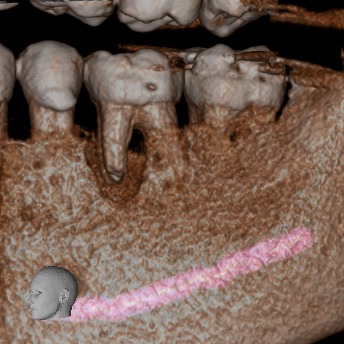

• Rápido – Cómodo – Eficaz: Las imágenes obtenidas con nuestros equipos son altamente detalladas, mostrando los tejidos duros sin perder calidad.

Podemos analizar la posición y orientación de estructuras críticas como los nervios, las raíces dentales, los senos paranasales y la nariz, lo que ayuda a lograr un diagnóstico lo más preciso posible. Con nuestra tecnología de imagen avanzada, tu odontólogo podrá monitorear la estabilidad a largo plazo de tus restauraciones dentales, de esta forma se podrá obtener el resultado estético que deseas con tu tratamiento.